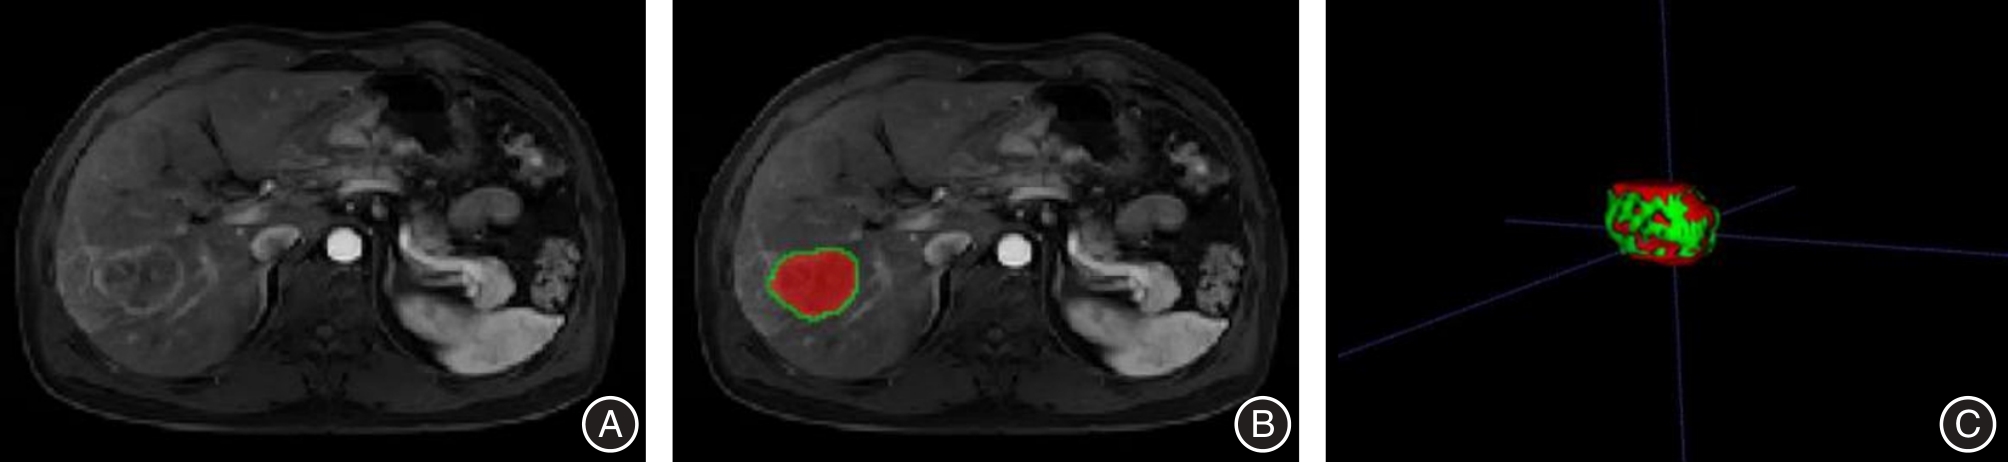

Huiliang CAI,Qianying ZHANG,Ying HUANG,Weisheng PENG,Chengli WANG,Cuiting YANG,Na DENG,Sizhu ZHANG,Nina XU,Xiaobing HAN. Assessments of ki⁃67 expression in hepatocellular carcinoma using enhanced MRI intratumoral and peritumoral radiomics and clinical imaging features[J]. The Journal of Practical Medicine, 2025, 41(15): 2311-2319.